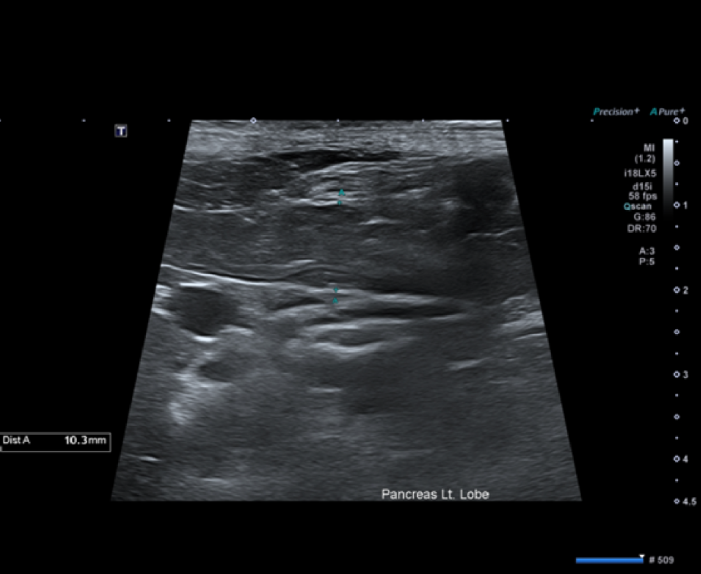

- 복부초음파

췌장의 실질은 저에코를 나타내고 있고 주변 지방은 에코가 상승되어 있습니다.

종합하였을 때 코코의 구토의 원인은 급성 췌장염으로 진단 되었습니다.

또한 복부 초음파 재검사에서 이전에 관찰되던 췌장 주변 지방의 고에코성 변화와 부종 소견이 개선되는 것으로 확인되었습니다.